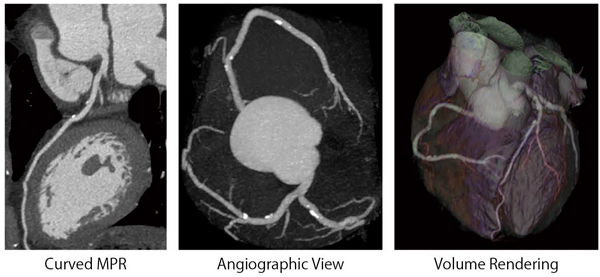

64列CTが登場して以来,心臓CT検査は加速度を増すように普及し,いまでは一般的に行われる検査の1つになったと考えられる。これは,2008年の診療報酬改定において,冠動脈CT加算が設けられたことからもうかがい知ることができる。心臓CT検査は,血管造影検査と比較して侵襲性が少なく,3次元的な立体把握が簡便であり,そして,患者様においては経済的なメリットがあると報告されている。特に,NPV(negative predict value:陰性適中率)が非常に高いことから,これまで冠動脈狭窄病変の除外診断を目的としたスクリーニング検査として用いられることが多かった心臓CT検査ではあるが,最近では,精密検査やフォローアップなど多岐にわたって応用されるようになってきた。

しかし,依然として限界もある。高度石灰化病変における狭窄率評価,ステント内再狭窄の評価,CT値計測などの精度は,まだまだ改善の余地があるとされている。これらの問題の根本的な原因は,CT値の高い高吸収体の“blurring”によるボケの影響である。言い換えれば,空間分解能が向上すれば,これら複数の問題点を克服することができる。

CT750 HDは,ガーネットの結晶構造を利用した新しいX線検出器“Gemstoneディテクタ”を搭載している。この検出器は,従来のX線検出器と比較して,X線応答速度(Primary Speed)が約100倍*4の0.03μsec,40msec後残光特性(after grow)が1/4*4の0.001%まで改善しており,高速応答性が大きな特長の1つとなっている。この特長により,1回転中におけるサンプリング数の増加を可能とし,サンプリングを高密度化することで高分解能化を実現している。従来の64列CTと比較してサンプリング数が2.5倍*4となり,通常の撮影においては2496ビュー/回転,心臓撮影において1662ビュー/回転に増加したことで,面内空間分解能が33%*3向上した(図2)。

心臓CT検査の課題の1つとされている被ばく線量の低減に関して,CT750 HDは解決策を提供している。GEが世界に先駆けて発表・製品化を実現した心臓撮影法“SnapShot Pulse”と,逐次近似法を応用した新しい画像再構成法ASiRを併用することで,心臓CT検査における大幅な被ばく低減を実現している。SnapShot Pulseは,プロスペクティブゲーティング法を用いることで,従来の一般的な心臓CT検査で受ける被ばく線量と比較して,最大83%の被ばく線量を低減*4する。また,ASiRを用いれば,従来の方式と比較し,最大50%の管電流で撮影しても従来と同等の画像ノイズの再構成画像が得られる*4。これにより,従来の心臓CT検査と比較して,最大95%被ばく線量を低減*4することを可能としている(図4)。